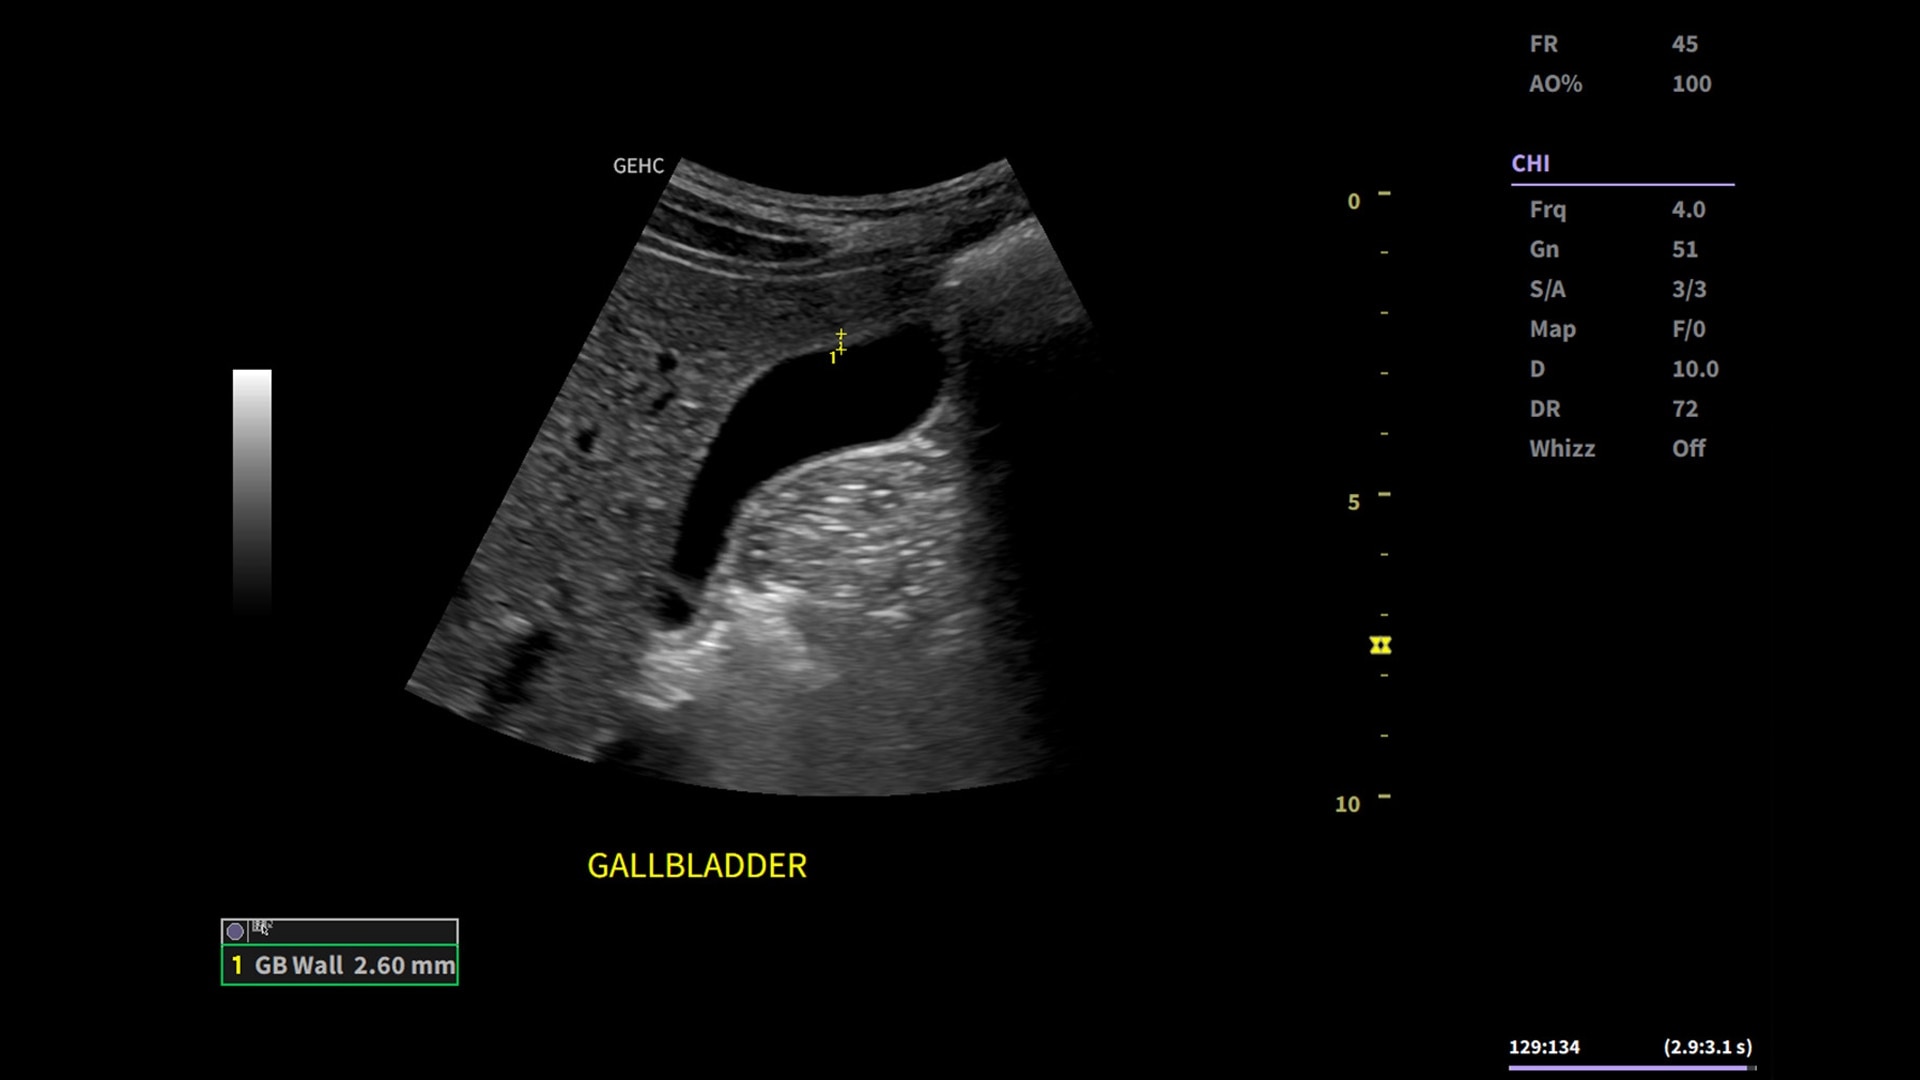

Whizz Label

AI-enabled labeling of the right kidney, gallbladder and liver

Powered by VisionBoost Architecture, Versana Premier provides optimal image quality so users can easily reach a diagnosis. Advanced clinical features help address challenging cases while automated tools help reduce scan time:

• Use automated labeling in the RUQ with Whizz Label

• Make automated 2D Measurements and Volume Calculations with Auto Contour, Auto Bladder, Whizz Follicle and Auto-IMT

• Assess liver, thyroid and breast nodules with Productivity Packages leveraging LI-RADS,® TI-RADS® and BI-RADS® criteria*